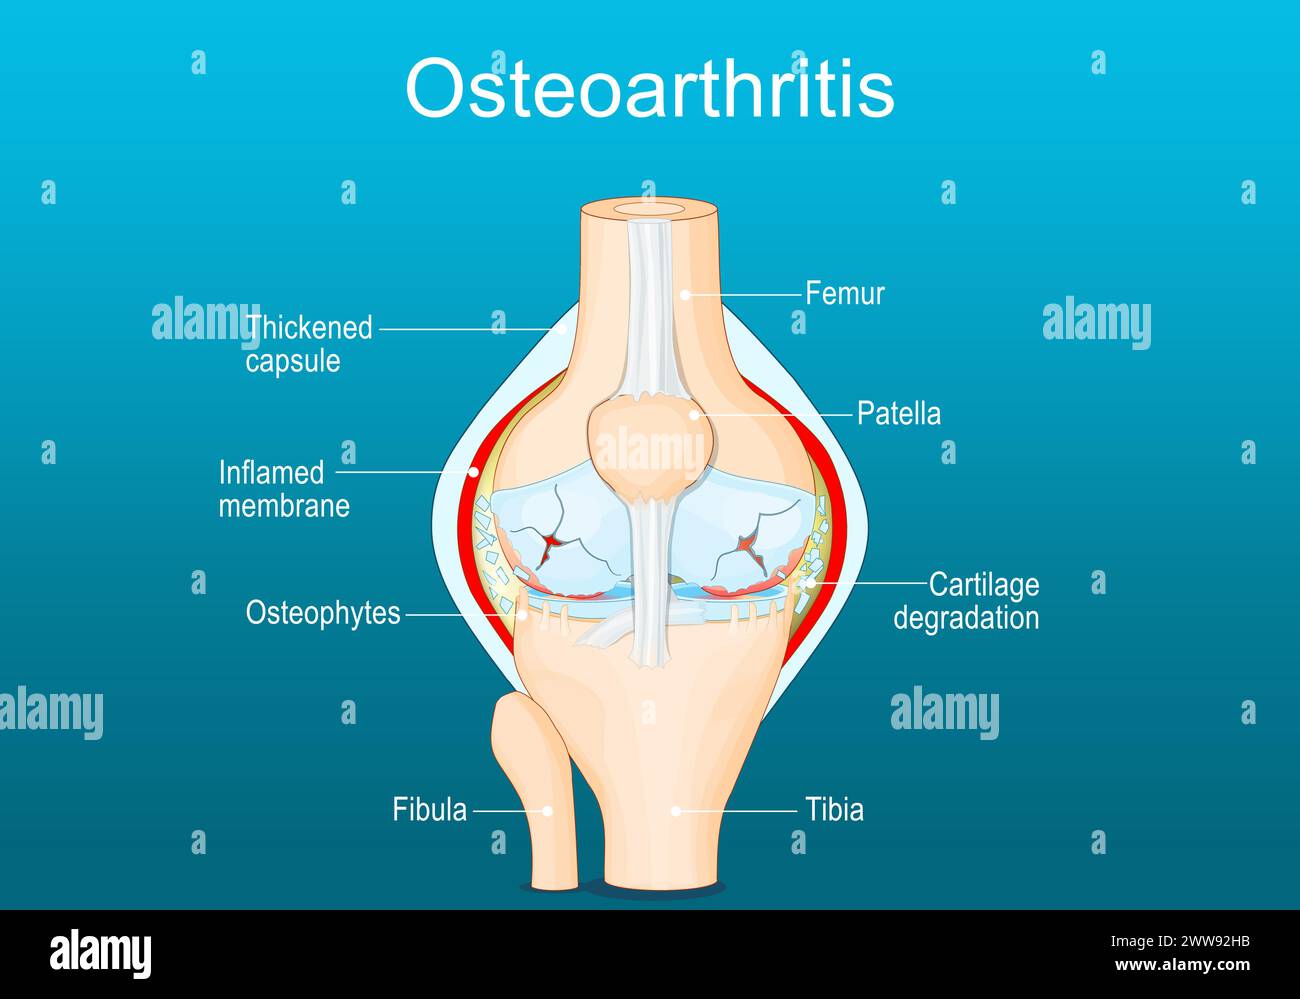

Osteoarthritis. Arthritis of a knee joint. Pain within a knee. Degenerative joint disease. Isometric Flat vector illustration Stock Vectorhttps://www.alamy.com/image-license-details/?v=1https://www.alamy.com/osteoarthritis-arthritis-of-a-knee-joint-pain-within-a-knee-degenerative-joint-disease-isometric-flat-vector-illustration-image600718535.html

Osteoarthritis. Arthritis of a knee joint. Pain within a knee. Degenerative joint disease. Isometric Flat vector illustration Stock Vectorhttps://www.alamy.com/image-license-details/?v=1https://www.alamy.com/osteoarthritis-arthritis-of-a-knee-joint-pain-within-a-knee-degenerative-joint-disease-isometric-flat-vector-illustration-image600718535.htmlRF2WW92HB–Osteoarthritis. Arthritis of a knee joint. Pain within a knee. Degenerative joint disease. Isometric Flat vector illustration